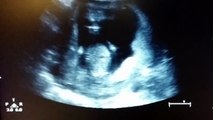

Une femme aveugle reçoit l'échographie en 3D de son bébé

Une échographie montre un bébé frapper dans ses mains

Une maman aveugle voit son bébé pour la 1ere fois